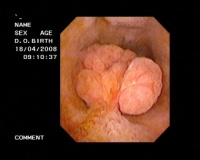

1.B超检查 方法灵活、准确、无创伤、可重复、价廉、易为众多患者接受,能准确地显示息肉的大小、位置、数量、囊壁的情况。B超典型的表现为胆囊壁有点状、小块状、片状的强或稍强回声光团,其后多无声影,可见到球状、桑葚状、乳头状及结节状突出,甚至可显示出息肉的蒂。杨汉良等报道B超对PLG检出率为92.7%,特异性94.8%,假阳性5.2%,准确性明显高于CT,认为BUS能清晰地显示PLG的部位、大小、数目及局部胆囊壁的变化,是一种简便可靠的诊断方法。

胆囊息肉三维超声成像

2.三维超声成像 可使胆囊具有空间方位的立体感,透声性好,有直视胆囊剖面的效果,可弥补二维显像某些不足。不仅可观察胆囊息肉的大小形态,更可分清息肉和胆囊壁的关系,尤其在胆囊后壁的息肉二维显像常不能清楚地分辨是否有蒂以及蒂与胆囊壁附着的范围和深度。三维重建能通过不同切面的旋转来观察病变的连续性及病变表面的情况等信息,有助于提高胆囊息肉与胆囊腺瘤或癌肿的鉴别。王连生等报道用三维超声成像检查18例胆囊内病变,最大直径为5.5cm,最小直径0.3cm,其中5例为多发性息肉,9例为单发性息肉,4例胆囊癌均为多发占位病变。三维超声成像与术中所见基本一致。